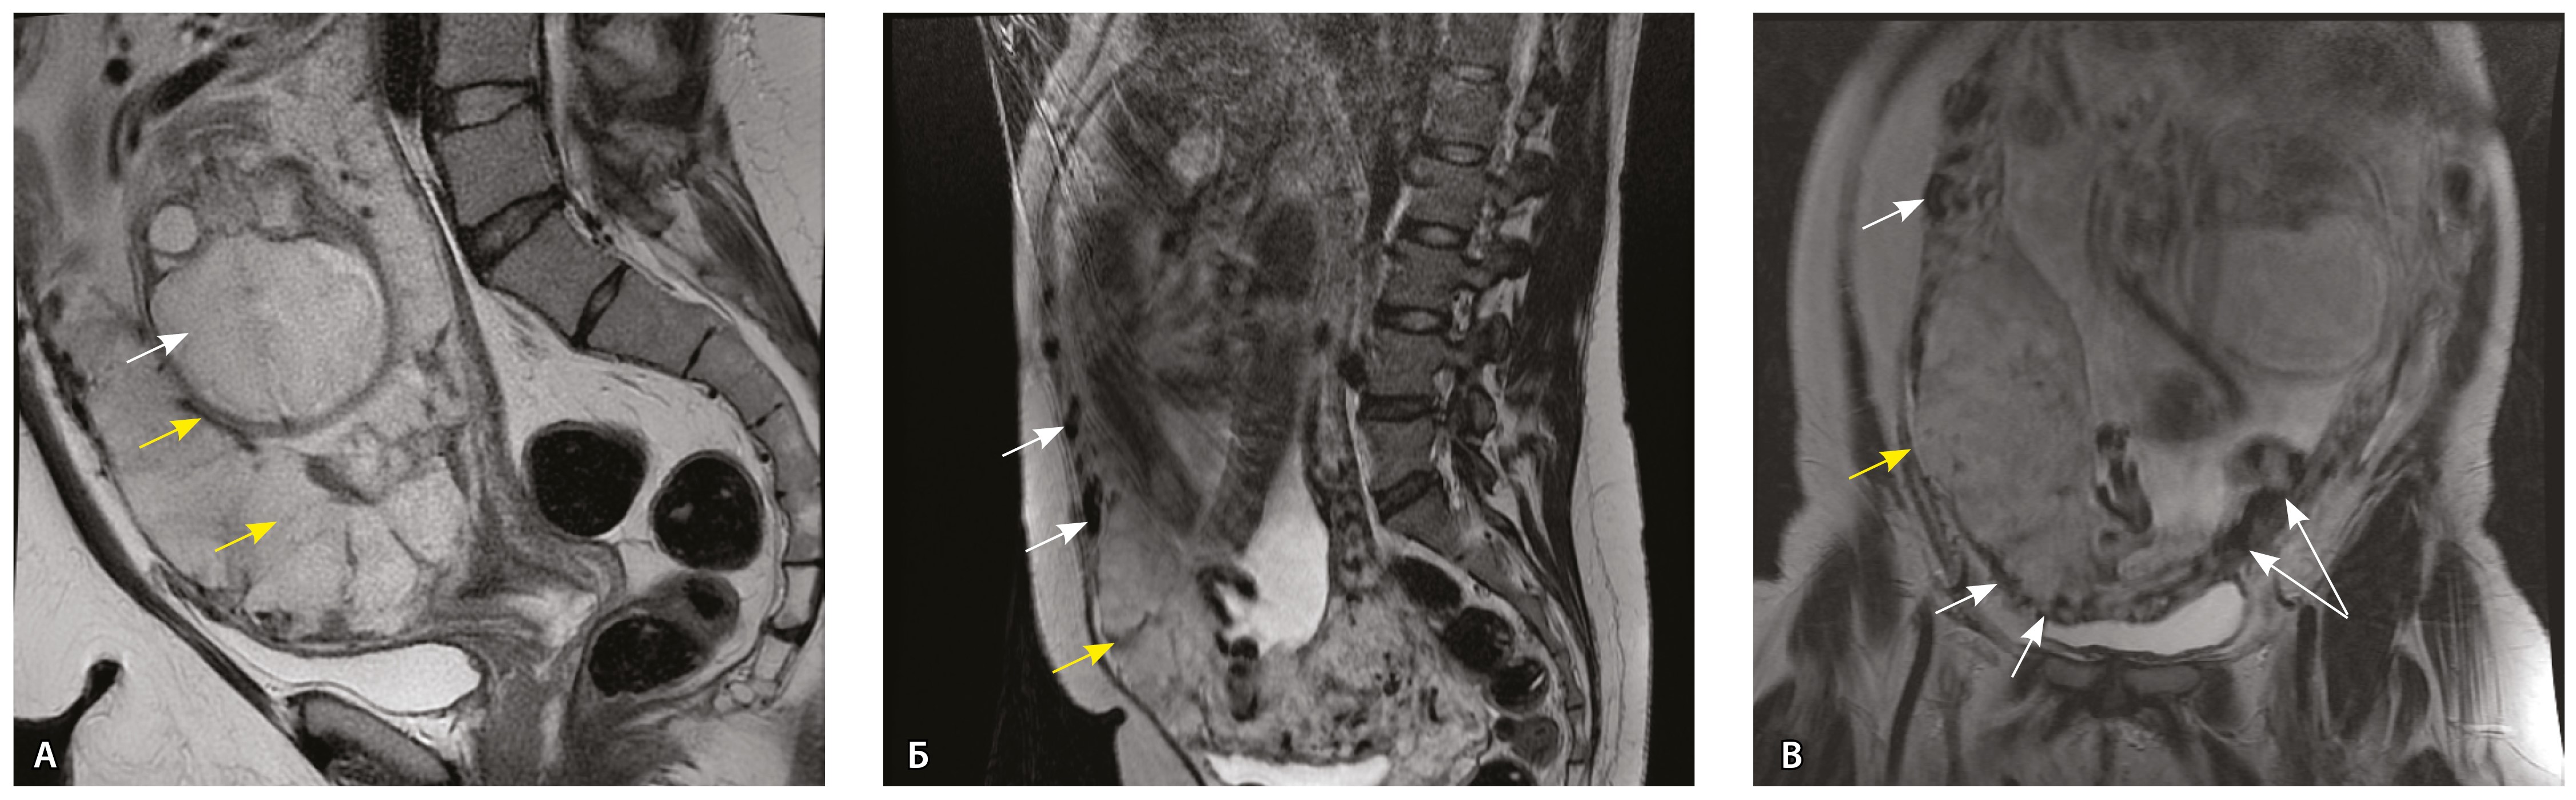

Сосуды 5-го типа. Наличие гиперваскуляризации за пределами матки по данным МРТ, на границе с мочевым пузырем с вовлечением его стенки, сосуды в области перешейка матки, параметрия, в том числе в сочетании с признаками фиброза, наличием рубцово-спаечных изменений и др. Можно предположить, что сосуды 5-го типа являются аналогом pl. рercreta PAS 3b, 3c (рис. 15).

Рис. 15. Беременность 34 недели, pl. percreta, PAS 3b по FIGO (A, Б), PAS 3c по FIGO (В). На магнитно-резонансных томограммах в режиме Т2-взвешенного изображения в сагиттальной (A, В) и аксиальной (Б) плоскостях определяется гиперваскуляризация в области выраженно истонченного нижнего маточного сегмента с распространением сосудов на заднюю стенку мочевого пузыря в области дна (белые стрелки), в область перешейка матки (желтые стрелки)

Данный вариант в патоморфологической картине наиболее сложен для оценки ввиду того, что такие структуры, как параметрий, перешеек матки, стенка мочевого пузыря, обычно не предоставляются в виде макропрепаратов, поэтому визуальные методы, в частности МРТ, могут с большей точностью оценить вовлеченность смежных структур. На микропрепаратах данный вариант инвазии плаценты сочетается с рубцово-спаечными изменениями задней стенки мочевого пузыря с нижним маточным сегментом (рис. 16).